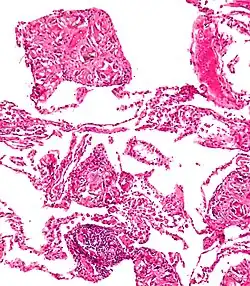

La Talcosis es una enfermedad pulmonar causada por la inhalación de talco.

Se ha relacionado con silicosis resultante de la inhalación de talco y silicatos. También está ligado al consumo de heroína donde podría ser usado el talco utilizado como un adulterante para aumentar el peso en las ventas de calle, por lo que la inyección de heroína con talco diluido causa talcosis ..."[1]

La talcosis también puede surgir de la inyección de medicamentos destinados a la administración oral, como el talco está presente en muchas tabletas y cápsulas que son objeto de abuso por vía intravenosa , tales como benzodiazepinas , dextroanfetamina , y en la prescripción de narcóticos. It is one of several noted associations and possible risks of street heroin use.[2]